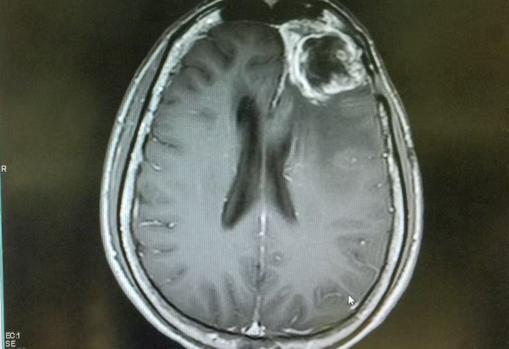

El glioblastoma es el más común y letal de los tumores cerebrales malignos. El tratamiento estándar incluye los tres ejes terapéuticos actuales: resección quirúrgica, radioterapia y quimioterapia con temozolomida .

Sin embargo, a pesar de la potencia del tratamiento, la supervivencia media no supera ... los 15 meses y apenas un 10% de los pacientes sobreviven más allá de los 5 años desde su diagnóstico.

La eficacia de los tratamientos es limitada debido a la capacidad de las células tumorales para invadir e infiltrar el tejido sano que las rodea, junto con su resistencia a la radio-quimioterapia. En este sentido, el manejo terapéutico actual del glioblastoma es meramente una efímera barrera a la inevitable recaída tumoral.